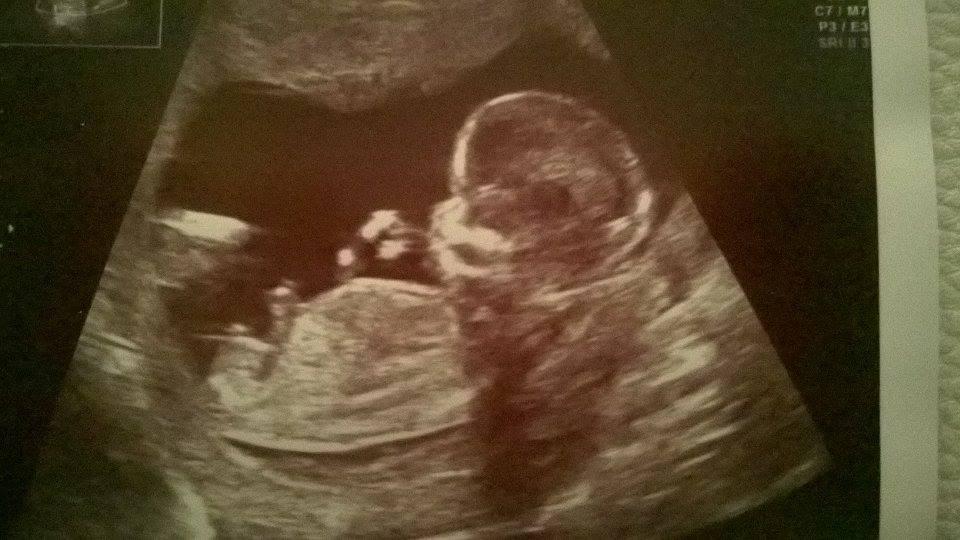

@kythos21 cez sono. Povedala som jej ze som mala bolesti a krvacala som a ona ma vysetrila podrobnejsie a nasla ju. Asi tyzden pred tym som bola normalne na poradni a nic nevidela. Nevravim ze to musis mat aj ty ale pre tvoj pokoj by som sla aspon ku gyn a povedala jej o tom. Ja osobne som nerobila hned paniku s pohotovostou ale pockala a na druhy den som sla ku gyn.